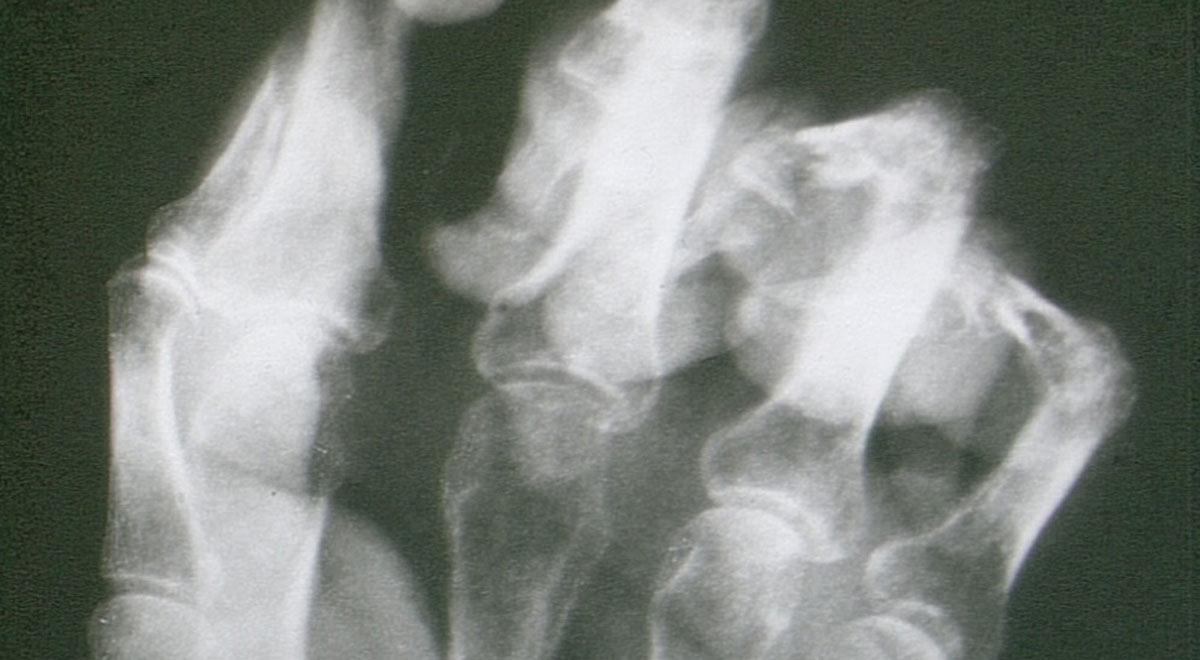

In dit artikel wordt aandacht geschonken aan de multidisciplinaire richtlijn Complex regionaal pijnsyndroom type I (CRPS-I). Aan de orde komen epidemiologie, pathofysiologie, predisponerende factoren, natuurlijk beloop en de belangrijkste conclusies en aanbevelingen ten aanzien van diagnostiek en therapie. Wat uitgebreider wordt stilgestaan bij het vaststellen van de belastbaarheid en begeleidingsadviezen zoals in de richtlijn in een apart hoofdstuk verwoord. Hoewel klinisch zeer relevant, komen de vele onderzoeken naar het nut van (aanvullende) diagnostiek en behandeling minder uitgebreid aan bod.